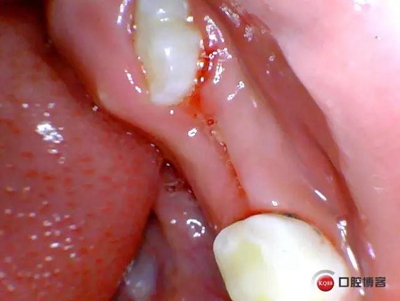

處理:*75局麻下拔除,壓迫止血,不適隨診。

一周后患者復(fù)診,拔牙創(chuàng)恢復(fù)良,制作*74口內(nèi)帶環(huán)并焊接,反復(fù)試戴合適后藻酸鹽取上下頜模型并發(fā)加工廠做保持器。電話預(yù)約復(fù)診時(shí)間。